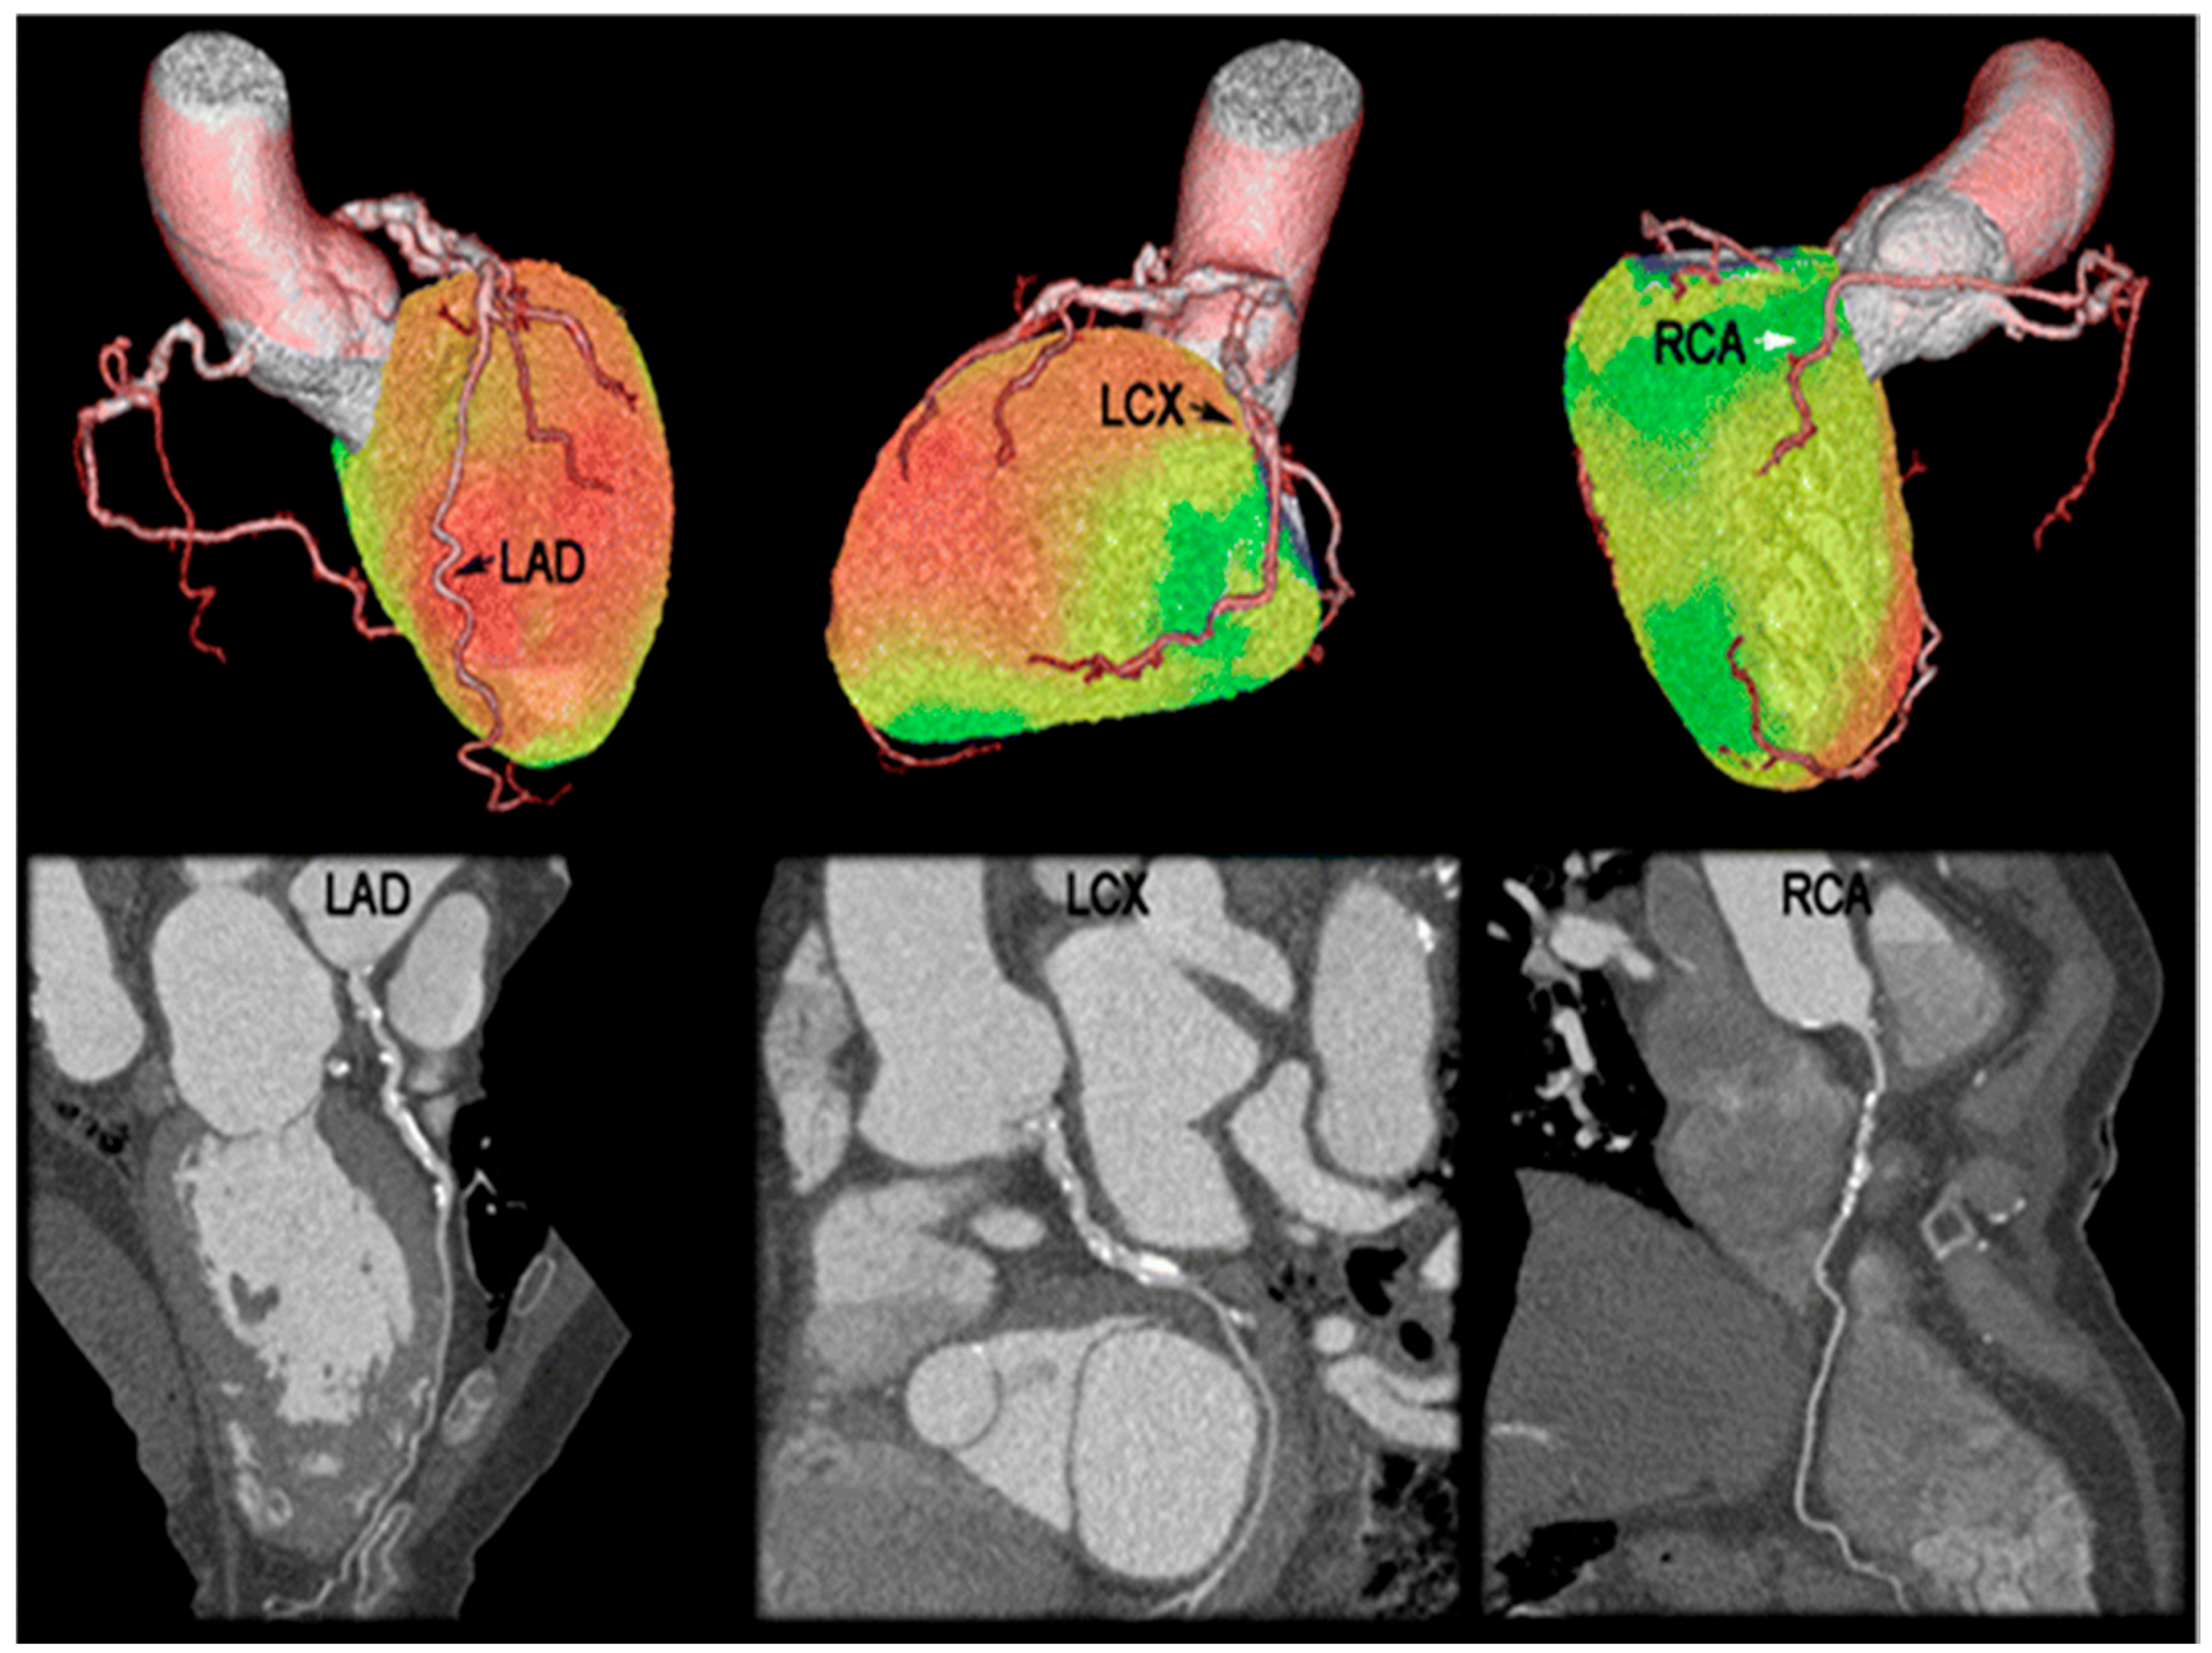

4. PET-CT Studies

4.1. MPI and Diagnostic Accuracy of CAD

4.2. Risk Stratification and Management